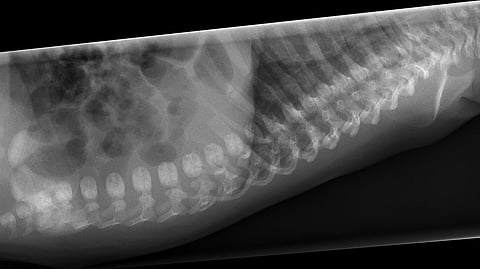

Quinn immediately ordered a standing X-ray of Ruth’s entire spine, as well as a full CT scan on her back. The tests and scans showed the complete loss of curvature in her lumbar spine, due to her previous spinal fusions, a severe degree of spinal malalignment when attempting to stand up straight, and new disc degeneration above her fusion. Quinn realized that surgery to treat the new problems above her fusion would require extending her fusion into her thoracic spine and cutting a wedge of bone through her prior fusion to restore normal spine curvature and “rebalance” Ruth’s spine. In February 2021, Quinn performed a 14-hour spinal fusion surgery on Ruth at Memorial Hermann-Texas Medical Center.